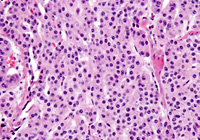

HE